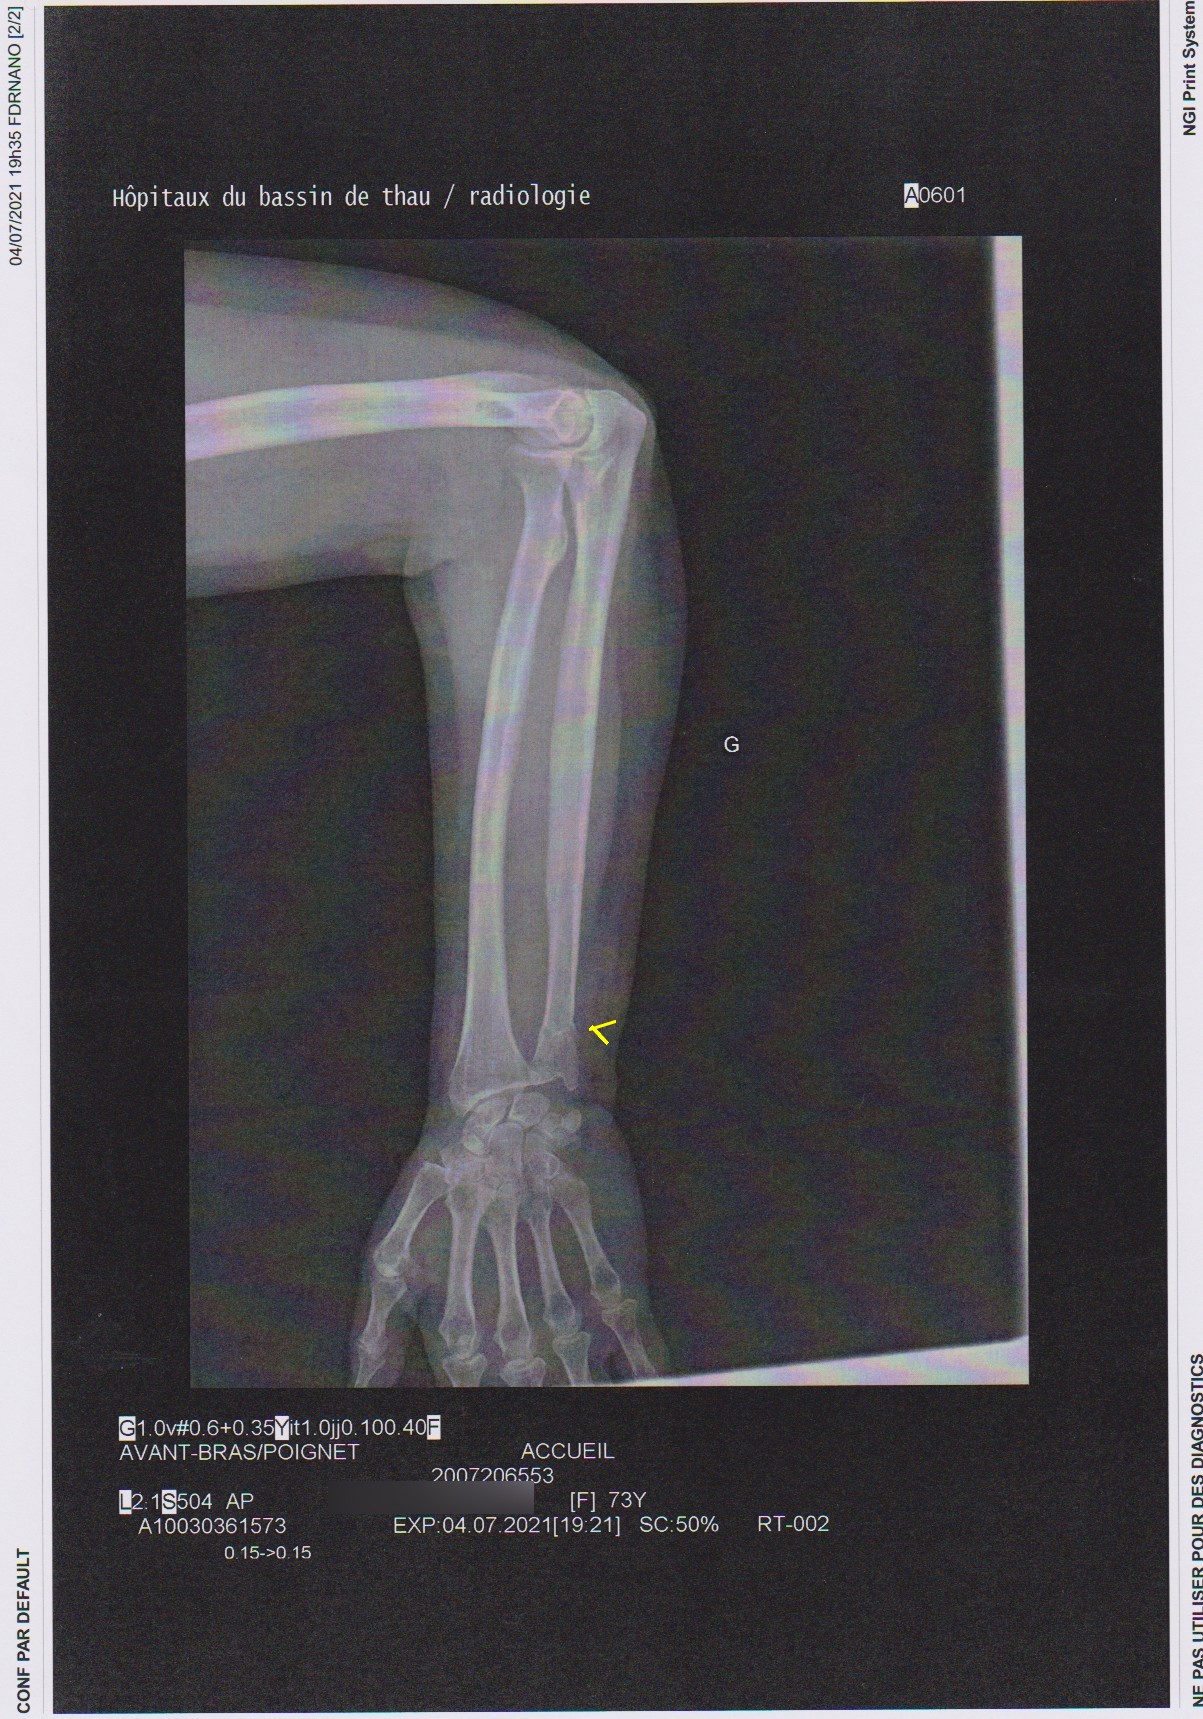

Comme vous le voyez il y a tout juste une petite trace de fracture du cubitus. Regardez la 2ème radio maintenant

Hé oui  il y a déplacement d’os ! Mon toubib a dit que le jour de l’accident ça aurait été normal mais pas 1 mois après !